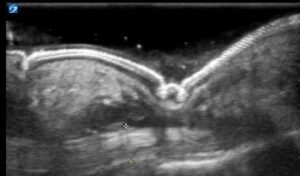

Figure 2: Long axis view of the finger with hypoechoic fluid superficial to the tendon. The anterior-posterior measurement of the tendon sheath can be compared to the contralateral unaffected hand to support a FTS diagnosis.